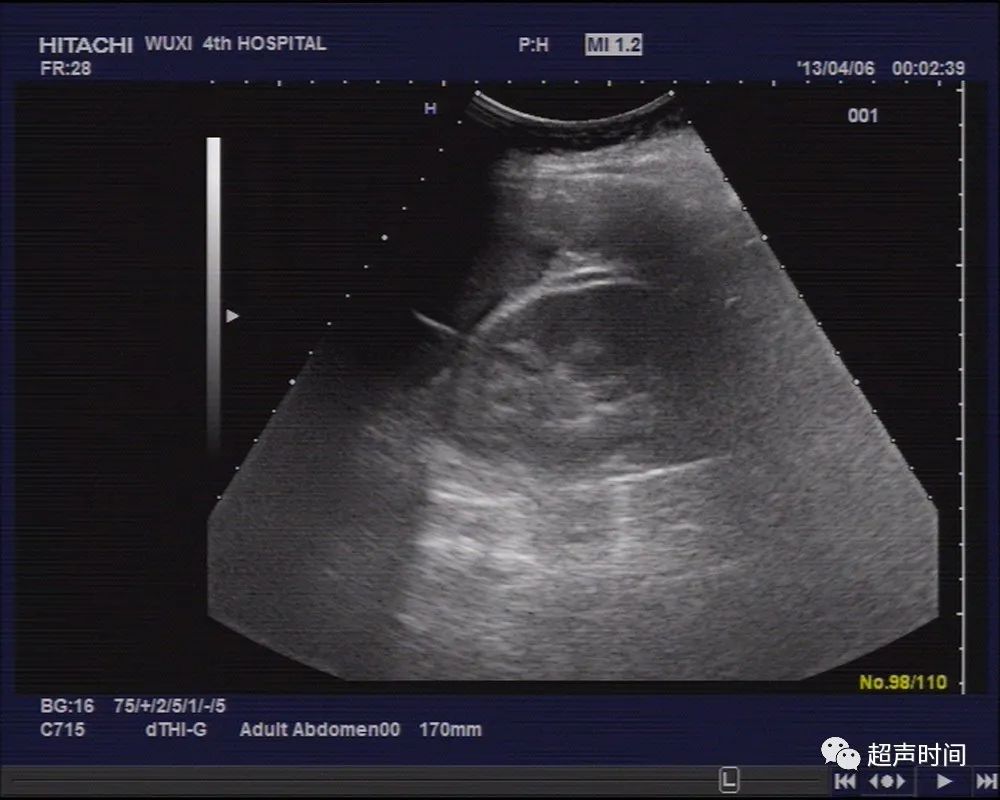

膀胱充盈可,子宫前位,稍大,肌层回声尚均,宫腔内未见明显孕囊结构,宫腔内可见低回声区,双卵巢显示不清,于左侧盆腔探及一类似妊娠囊结构,周边回声稍增强,其内可见一胎儿回声,头臀长约 71mm ,可见胎心、胎动(图 1~ 2 )。

图 1 左侧盆腔探及一类似孕囊结构,内见一头臀长约 70mm 的胎儿回声

图 2 胎儿可见胎心、胎动

左侧盆腔区域包块内可见胎儿及胎心胎动,孕囊周围可见较厚稍高回声包绕,可能是阔韧带周边网膜组织结构,左侧盆腔包块紧贴子宫后壁,其内胎儿位于子宫宫腔以外,但与子宫分界清晰,肝肾间隙、脾肾间隙、肠间隙、盆腔均可探及透声欠佳积液,提示存在有腹腔内出血。